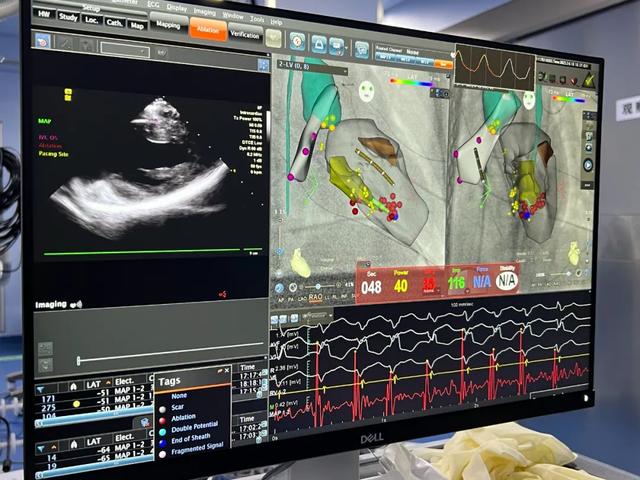

心腔内超声导管在CARTO3电生理标测系统中构建心脏三维模型,精准显示乳头肌和消融导管位置

术中运用2.6mm心腔内超声导管,同时与我所CARTO3电生理标测系统配合,放大影像至屏幕,在屏幕影像协助下熟练构建心腔三维模型,确定乳头肌位置,并反复调整导管位置,寻找消融靶点。通过这一“神兵利器”,江河副主任医师很快锁定乳头肌病灶,精准而稳定的贴靠消融导管,经过放电消融,顽固的室早消失,手术成功了。而且超声技术避免了频繁X线透视,大大减少了辐射,实现了复杂心律失常的绿色电生理。